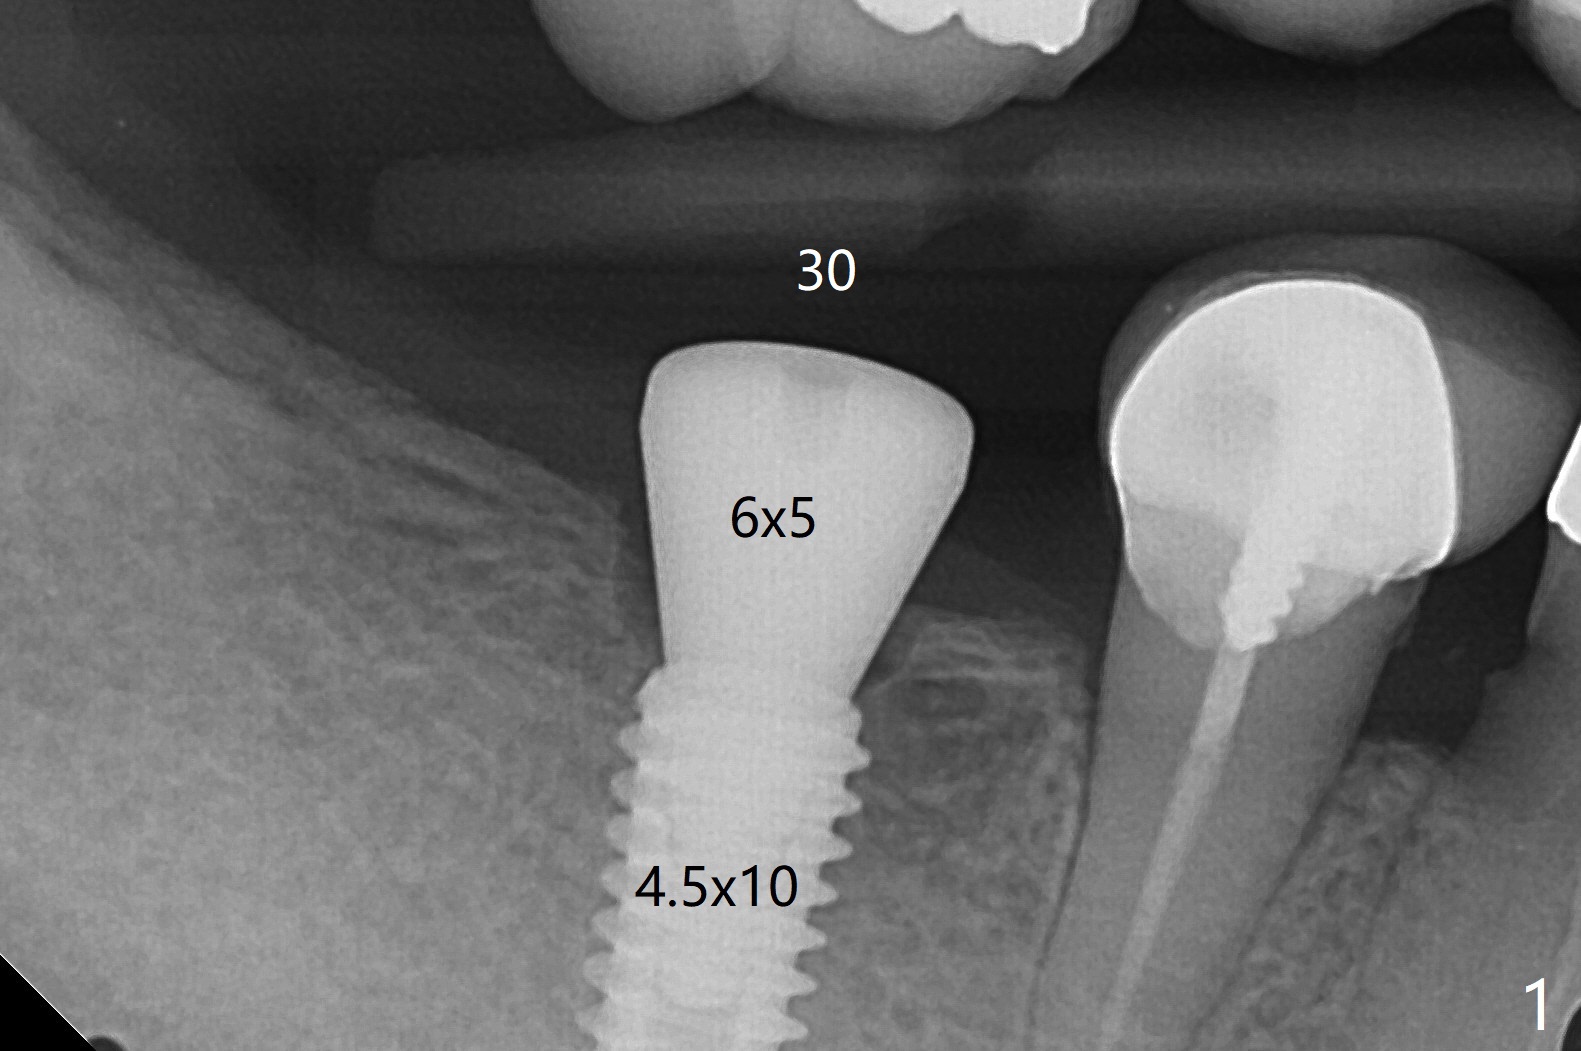

The female patient has limited mouth opening, complicated further by supraerupted opposing tooth. It is difficult to insert point drill and tap drill for #30 implant placement with guide. The former has to be inserted into the sleeve of the guide extraorally; two of them are placed intraorally together, while the tap drill is not used at all. When a 4.5x10 mm implant is placed, it is difficult to use #2 sensor to take PA. Finally a BW is taken with #2 sensor (Fig.1), while a PA is taken with #1 sensor (Fig.2). CT is taken to show clearance of the implant from the Inferior Alveolar Canal (Fig.3,4). To seat healing and later cemented abutments completely, a 5.5 mm profile drill is applied after implant placement; the outline is illustrated by red dashed line in Fig.1''. The elongated mesiolignual cusp of the tooth #3 has to be trimmed after placement of a 6x5 mm healing abutment. In fact trimming prior to osteotomy could solve the mouth opening partially. After removal of the 6x5 mm healing abutment, a 4.5x4(3) mm cemented abutment is incompletely seated (Fig.5 <) apparently due to proximity to the mesial crest (*). With reuse of a 4.6 mm profile drill, the abutment is fully seated (Fig.6), confirmed clinically by more clearance from the opposing tooth (Fig.7). Complete occlusal clearance is obtained by reduction of the opposing cusps without sensitivity since the tooth is nonvital (*). Return to No Deviation Xin Wei, DDS, PhD, MS 1st edition 05/28/2020, last revision 09/04/2020